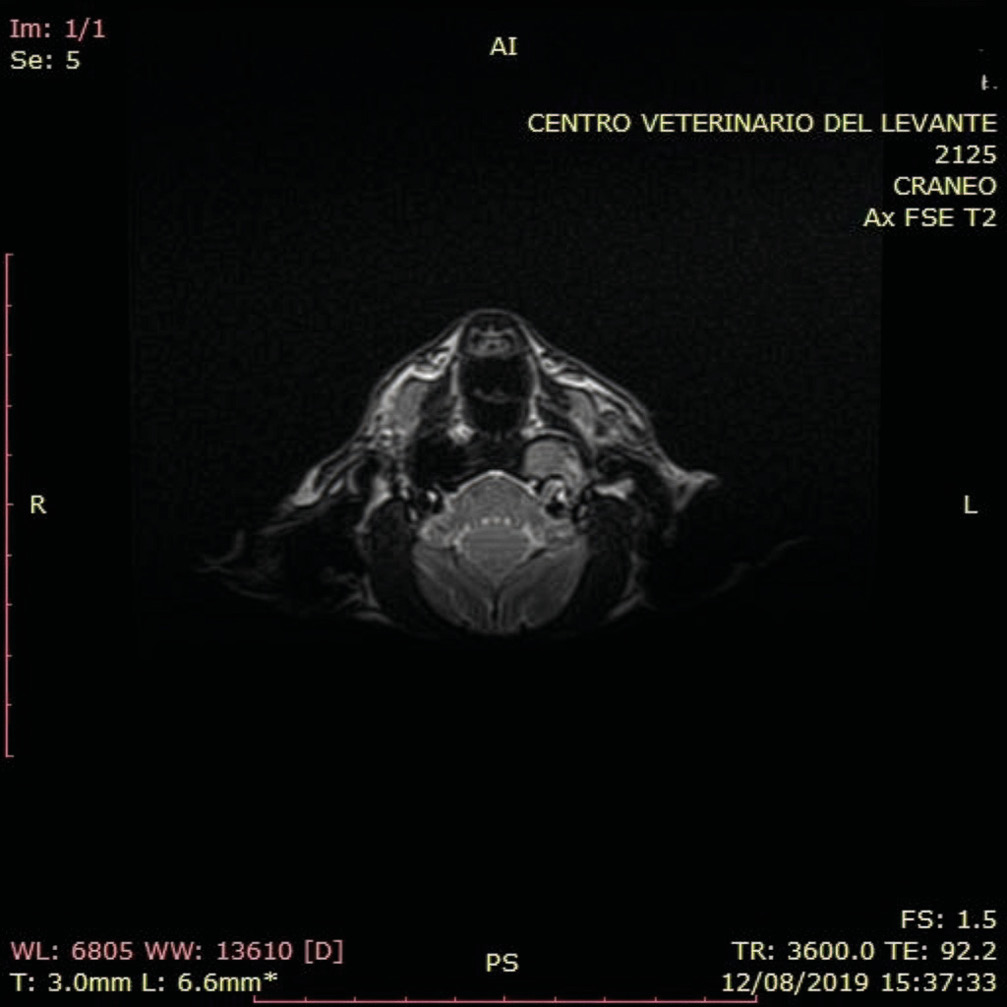

Tomografía computarizada (TC) y resonancia magnética (RMN)

La tomografía computarizada (TC) se considera la técnica de referencia para el estudio de las estructuras del oído medio. Permite valorar la integridad y el grosor del tímpano, la presencia de contenido líquido en oído medio, masas y alteraciones en la estructura ósea de la bulla y huesos adyacentes mediante la visualización de las estructuras anatómicas en sección transversal, evitando la superposición de estructuras característica de las radiografías.

El estudio de bullas timpánicas utiliza imágenes transversales contiguas de 1 a 3 mm, desde el área rostral a la bulla hasta el hueso temporal petroso. Se recomienda usar el campo de visión más pequeño posible y una técnica de alta densidad de mAs. El contraste yodado no suele administrarse, salvo sospecha de neoplasia u otitis interna. Las imágenes deben revisarse tanto en ventana ósea como de tejido blando.

En una posición adecuada en pacientes sin patología auricular ambas bullas se observan simétricas, permitiendo pequeñas variaciones anatómicas. El gas generalmente opaca la luz de la bulla timpánica y del conducto auditivo externo. La bulla timpánica presenta una pared delgada y delimitada. El conducto auditivo externo mantiene un grosor uniforme, sin evidencia de estrechamiento ni obstrucción luminal.

Los hallazgos tomográficos característicos de la otitis media comprenden el engrosamiento y la irregularidad de la pared de la bulla timpánica, la lisis ósea, presencia de material de densidad de tejido blando compatible con líquido o contenido tisular en su interior, así como signos asociados de otitis externa (imagen 8).

La resonancia magnética (RMN) permite una mejor visualización de los tejidos blandos y de las estructuras del oído interno, resultando útil en la diferenciación de la enfermedad vestibular central frente a la periférica.

Al igual que en la TC, el paciente se coloca en decúbito esternal con la cabeza en la bobina de radiofrecuencia y las extremidades anteriores orientadas hacia caudal. Se pueden usar los mismos puntos de referencia que en la TC para facilitar el posicionamiento.

La RMN de otitis media muestra material de intensidad de señal intermedia en la bulla timpánica en las imágenes ponderadas en T1 e hiperintensidad en las imágenes ponderadas en T2. Tras administrar un agente de contraste, puede observarse un realce del margen interno en T1. En imágenes ponderadas de T2, una apariencia laminada de intensidades de señale alta y baja sugiere cronicidad, representando las zonas hipointensas tejido fibroso (imagen 9). Los cambios óseos leves de la bulla timpánica son difíciles de valorar por RMN.